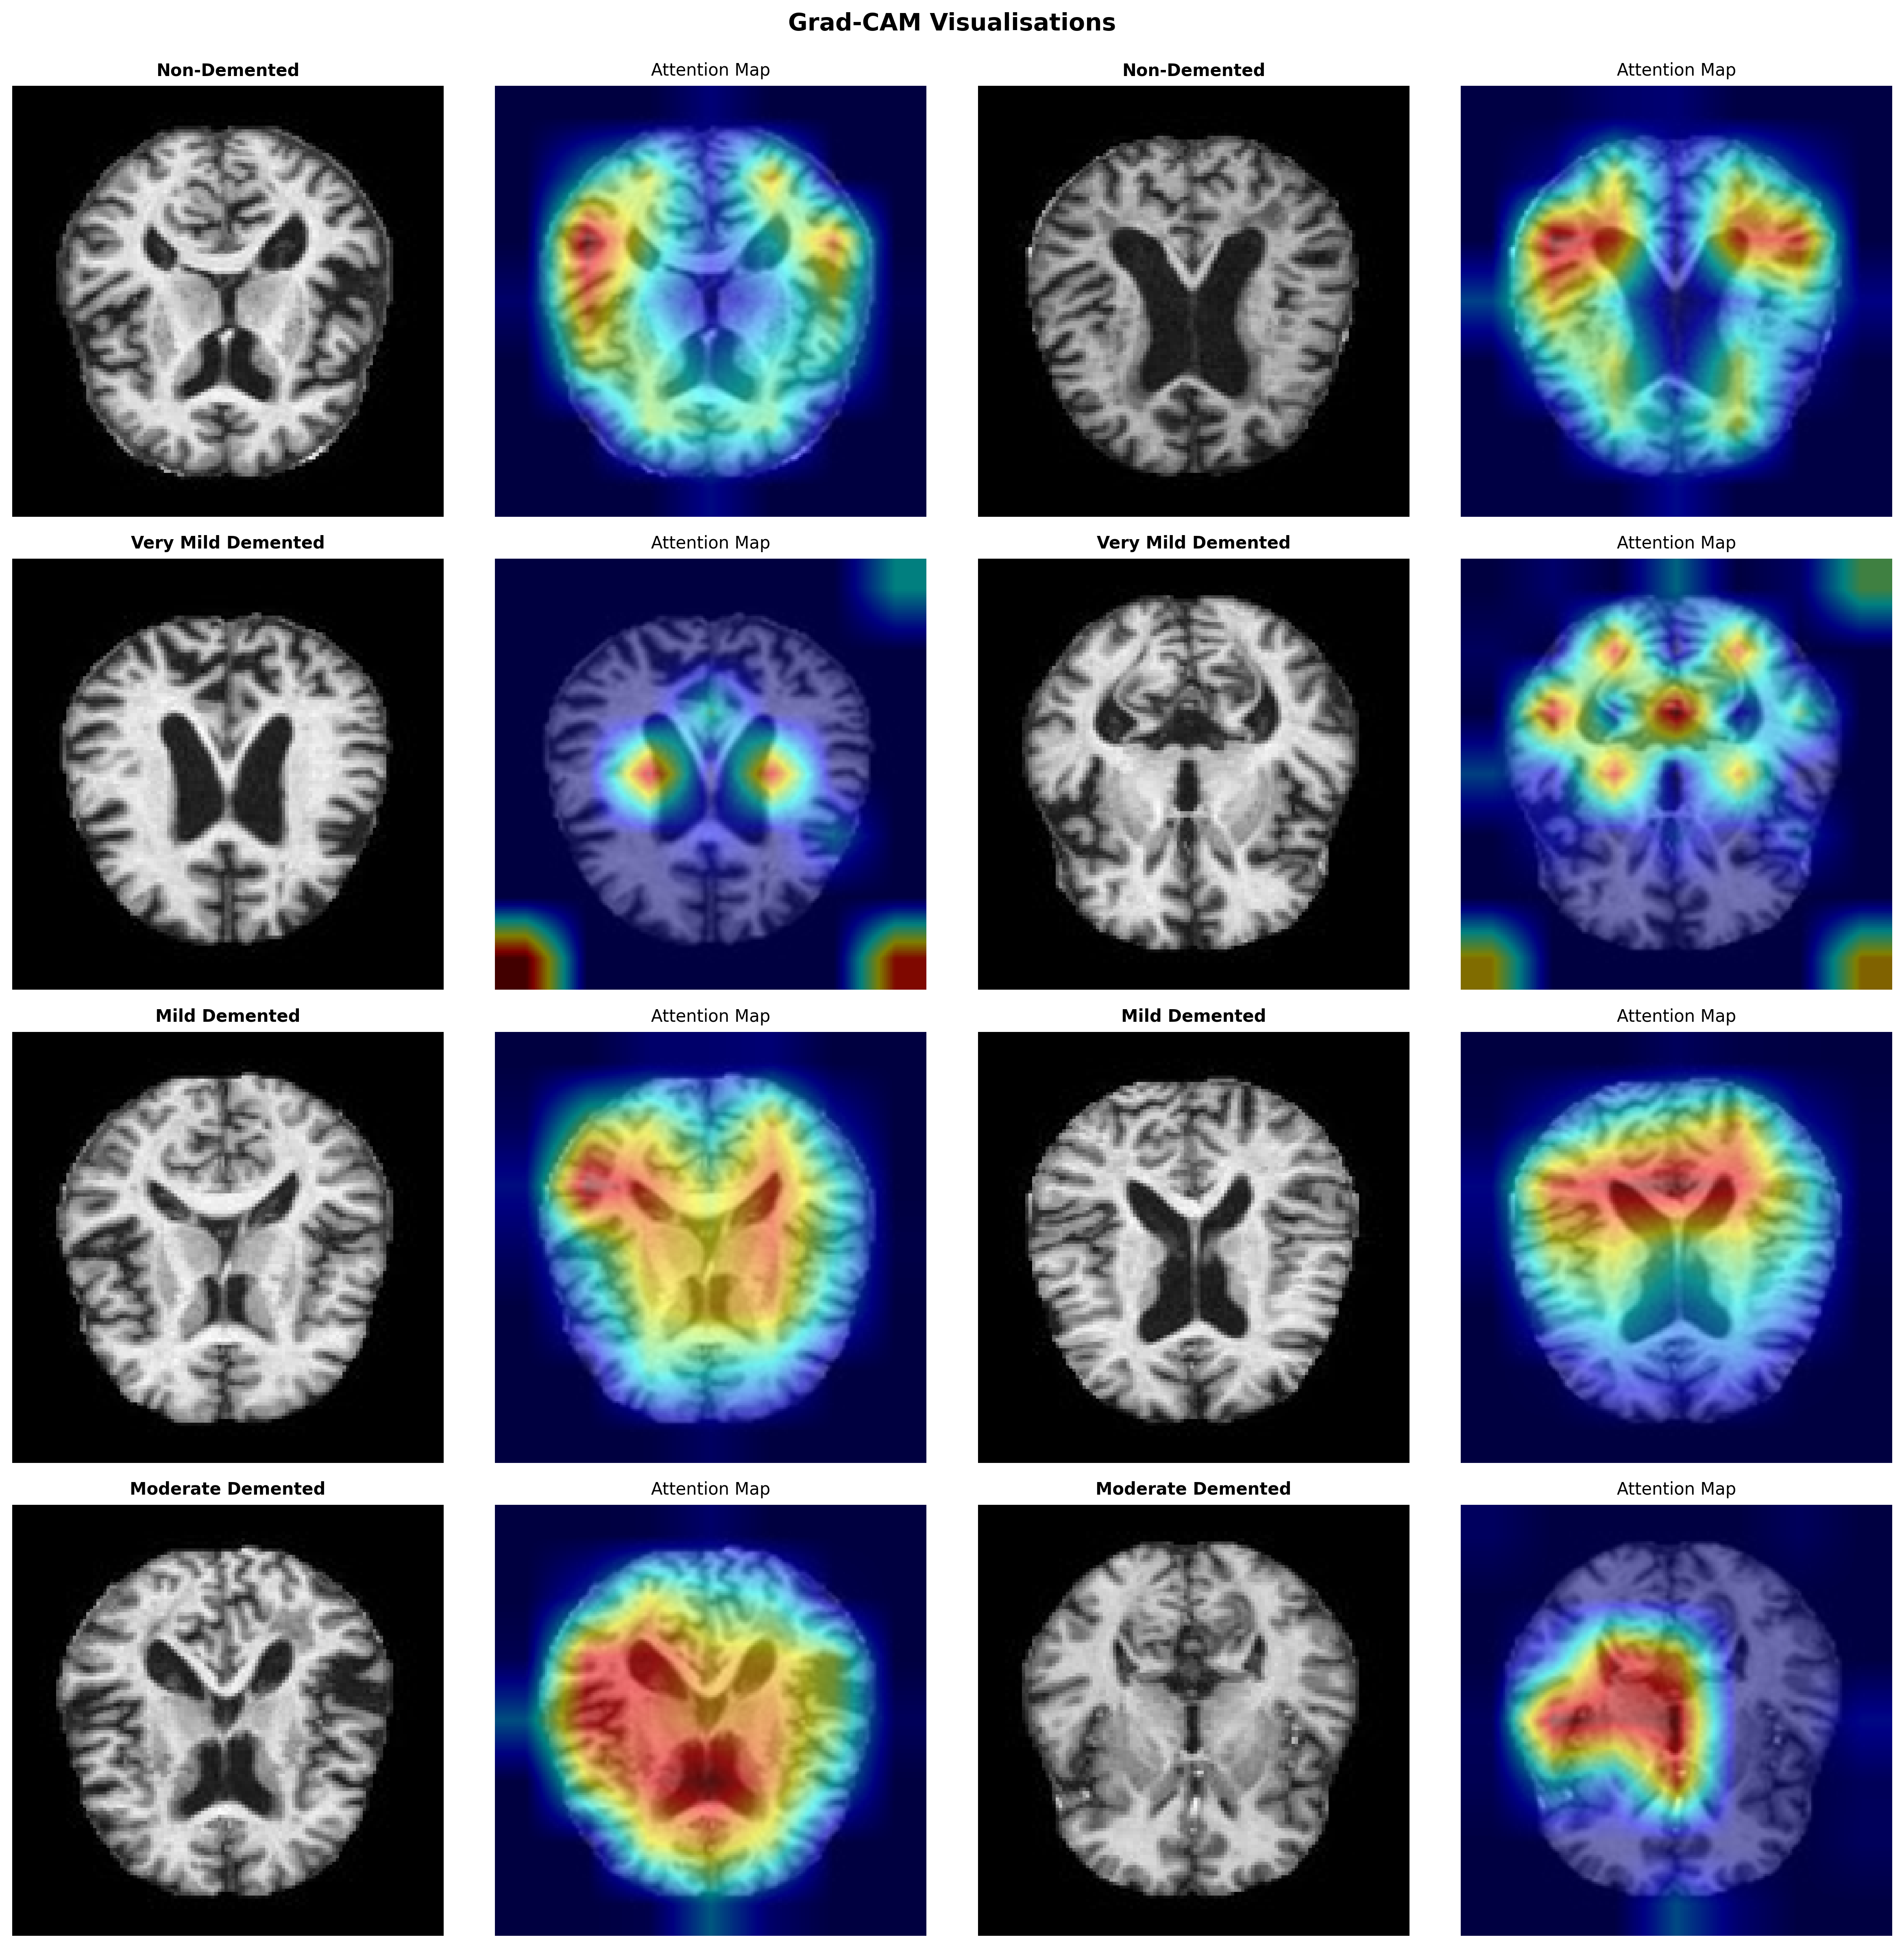

A key focus was ensuring the system produces meaningful probability estimates rather than overconfident predictions. Post-hoc temperature scaling was applied to improve probabilistic calibration, and Grad-CAM visualisations were used to verify that the model attends to anatomically plausible brain regions associated with Alzheimer’s pathology.